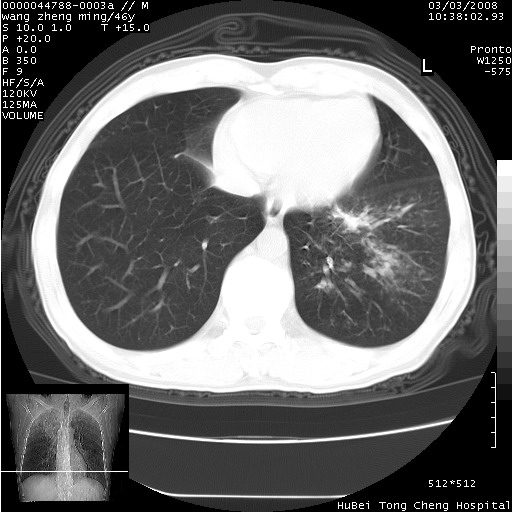

以下是引用卜一在2008-3-22 1:37:00的发言:[br]右肺实质性肿块,边缘不整,明显见毛刺征 分叶征及胸膜凹陷征,右上叶支气管明显变窄,远端散在的片状 斑片状实变影。另:左肺门较大肿块,支气管受累 变窄,远侧见阻塞性肺炎。纵隔内见肿大淋巴结。多考虑:右肺周围性肺癌伴左肺门 纵隔淋巴结转移!